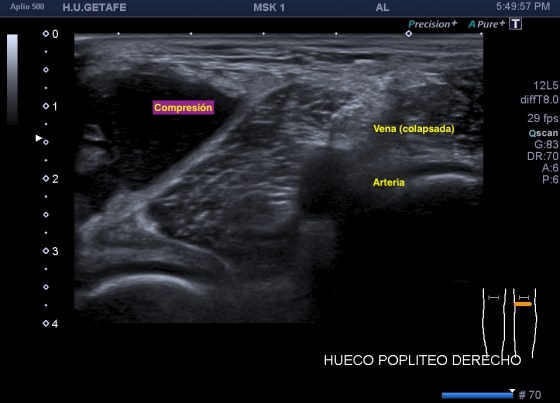

Recuerdo la importancia de comprobar siempre la permeabilidad de los vasos del hueco poplíteo con este tipo de patologías, el parecido de los síntomas de un quiste de Baker roto y la TVP puede ser muy similar y sin embargo, la TVP es una patología potencialmente peligrosa. Para ello pide al paciente que suba la pierna afectada por encima de su otra pierna para poder hacer que el retorno venoso sea más evidente y poder estudiar los mencionados vasos, sobre todo, su vena, claro.

La compresión con la sonda del hueco poplíteo establece la permeabilidad de la vena poplitea. Normalidad por tanto, manda, el comportamiento de la vena, compresible, y no el uso del doppler, por eso me permito el lujo de enseñarte la técnica sin el uso del doppler color. Línea roja: Si la vena no se colapsa.